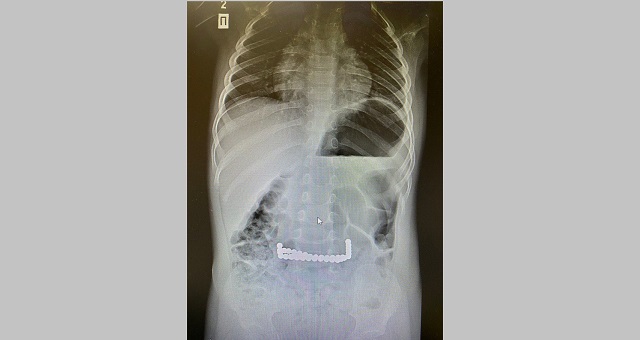

Хирурги Камского детского медицинского центра (КДМЦ) путем эндоскопической операции извлекли из желудка юного пациента 40 магнитных шариков, которые он проглотил. Об этом сообщила пресс-служба медучреждения.

В КДМЦ отметили, что это второй случай, зарегистрированный в этом году в медцентре. Ранее медикам уже приходилось спасать девочку, которая проглотила 13 таких же шариков. Тогда магниты прошли по желудочно-кишечному тракту, притянулись к друг-другу и образовали цепочку-кольцо вокруг кишечника.